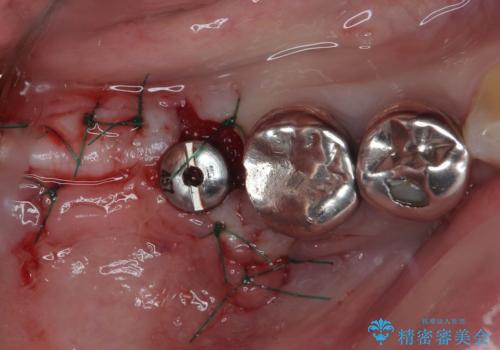

- 「歯を抜いたので、インプラントを入れてほしい」という主訴で来院された患者様です。

他院で歯根破折により抜歯をしたとのことでした。

CTにより残存骨量を確認しインプラント埋入を行っていくこととしました。

今後手前の根管治療を行っている歯が歯根破折を起こして抜歯になる可能性を想定して手前の歯に平行にインプラント埋入を行っています。